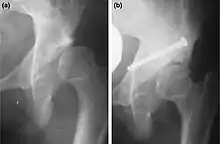

a. X-ray of a hip after capsulorrhaphy and Dega surgery.

b. Same hip after addition of Chiari medial displacementosteotomy.[4]